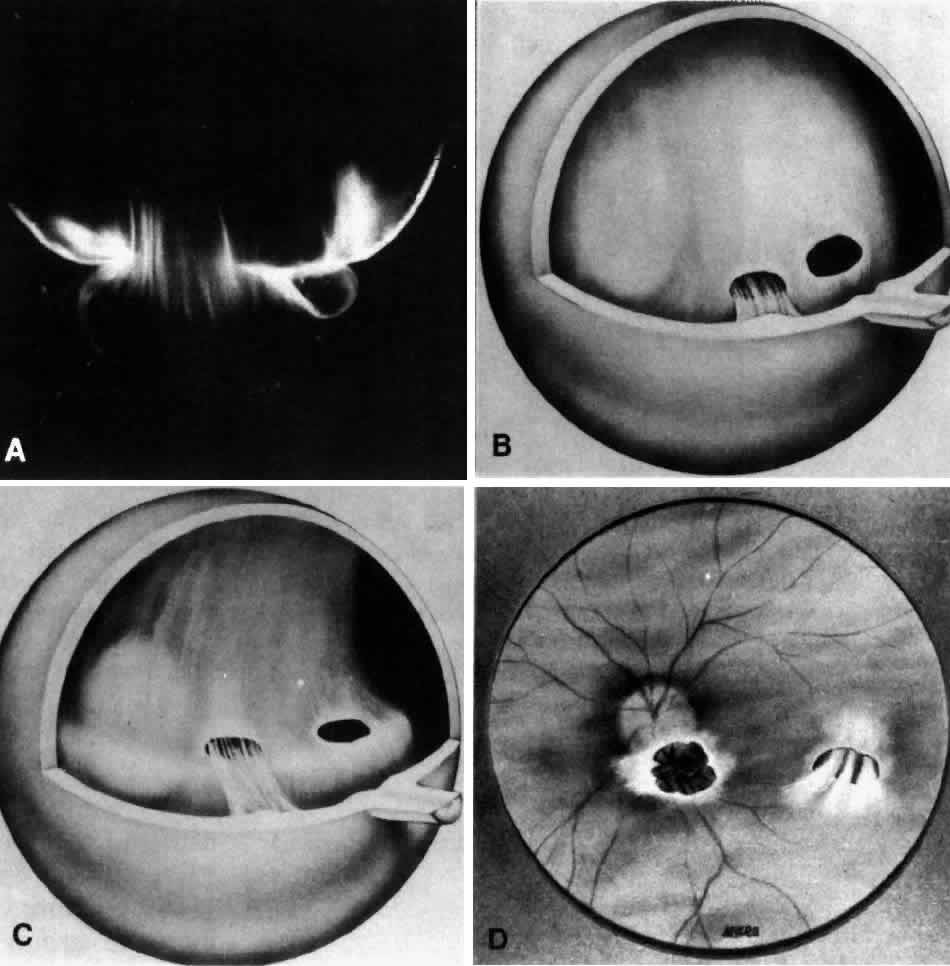

Fig. 15. Anomalous posterior vitreous detachment. Vitreous can remain attached to the macula even in the presence of posterior vitreous detachment. In such cases, vitreous can extrude through the premacular vitreous cortex and fibers can insert into the macula. B, C, and D are an artist's rendition of this phenomenon. A demonstrates actual vitreous extrusion into the retrocortical space in a postmortem human specimen (see Fig. 4D) (B and C adapted from Jaffe NS: The Vitreous in Clinical Ophthalmology. St. Louis, CV Mosby, 1969; D adapted from Jaffe NS: Vitreous traction at the posterior pole of the fundus due to alterations in the posterior vitreous. Trans Am Acad Ophthalmol Otolaryngol 71:642, 1967)

Fig. 4. Human vitreous structure is visualized by darkfield slit microscopy. All photographs are oriented with the anterior segment below and the posterior pole above. Photographs are sequential, beginning in the upper left hand corner and moving left to right. A. Posterior vitreous in the left eye of a 52-year-old man. The corpus vitreous is enclosed by the vitreous cortex. There is a hole in the prepapillary (small, to the left) vitreous cortex. B. Posterior vitreous in a 57-year-old man. A large bundle of prominent fibers is seen coursing anteroposteriorly and entering the retrohyaloid space through the premacular vitreous cortex. C. Same view as B at higher magnification. D. Posterior vitreous in the right eye of a 53-year-old woman. There is posterior extrusion of vitreous out the prepapillary hole (to the right) and premacular (large extrusion to the left) vitreous cortex. Fibers course anteroposteriorly in the central vitreous and out into the retrocortical (formerly preretinal, before dissection) space. E. Horizontal optical section of the same specimen as D at a different level. A large fiber courses posteriorly from the central vitreous and inserts into the premacular vitreous cortex. F. Same view as E at higher magnification. The large fiber has a curvilinear appearance because of traction by vitreous extruding into the retrocortical space. However, because of its attachment to the posterior vitreous cortex the fiber arcs back to its point of insertion. G. Anterior and central vitreous in a 33-year-old woman. Cloquet's canal is seen forming the retrolental space of Berger. H. Anterior and peripheral vitreous in a 57-year-old man. The specimen is tilted forward to enable visualization of the posterior aspect of the lens and the peripheral anterior vitreous. Behind and to the right of the lens there are fibers coursing anteroposteriorly that insert into the vitreous base. These fibers “splay out” to insert anterior and posterior to the ora serrata. (A, E, and F: Sebag J, Balazs EA: Pathogenesis of cystoid macular edema: An anatomic consideration of vitreoretinal adhesions. Surv Ophthalmol 28[suppl]:493, 1984; B and C: Sebag J, Balazs EA: Morphology and ultrastructure of human vitreous fibers. Invest Ophthalmol Vis Sci 30:187, 1989)